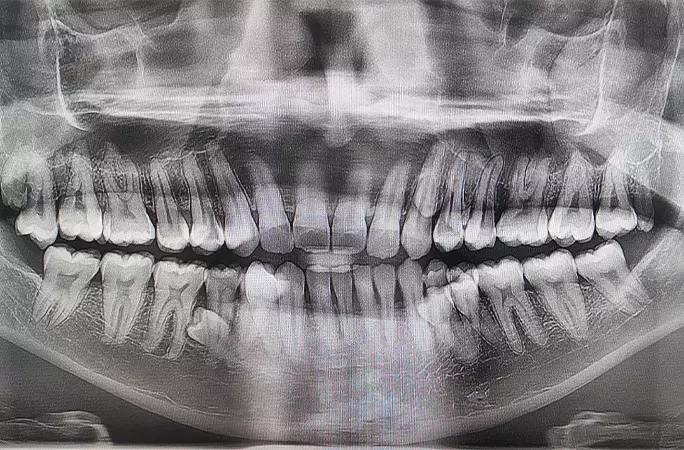

11일 기네스 세계기록에 따르면, 말레이시아 남성 프라탑 무니안디(33)는 최근 ‘최다 치아 보유 남성’ 부문에 이름을 올렸다. 그의 치아 개수는 총 42개로, 일반 성인 치아 개수(32개)보다 10개 더 많다.

앞서 프라탑은 두 명의 치과의사의 검진을 통해 치아 개수를 확인했다. 검사 결과, 그는 42개 치아 외에도 잇몸 속에 매복한 치아가 2개 더 있는 것으로 나타났다.

한편, 치아가 32개(성인 기준)보다 많이 난 것을 의학적으로는 ‘다발성 과잉치증’이라고 한다. 1~2개 과잉치는 종종 발견되지만, 프라탑처럼 10개씩 과잉치가 확인되는 경우는 많지 않다.